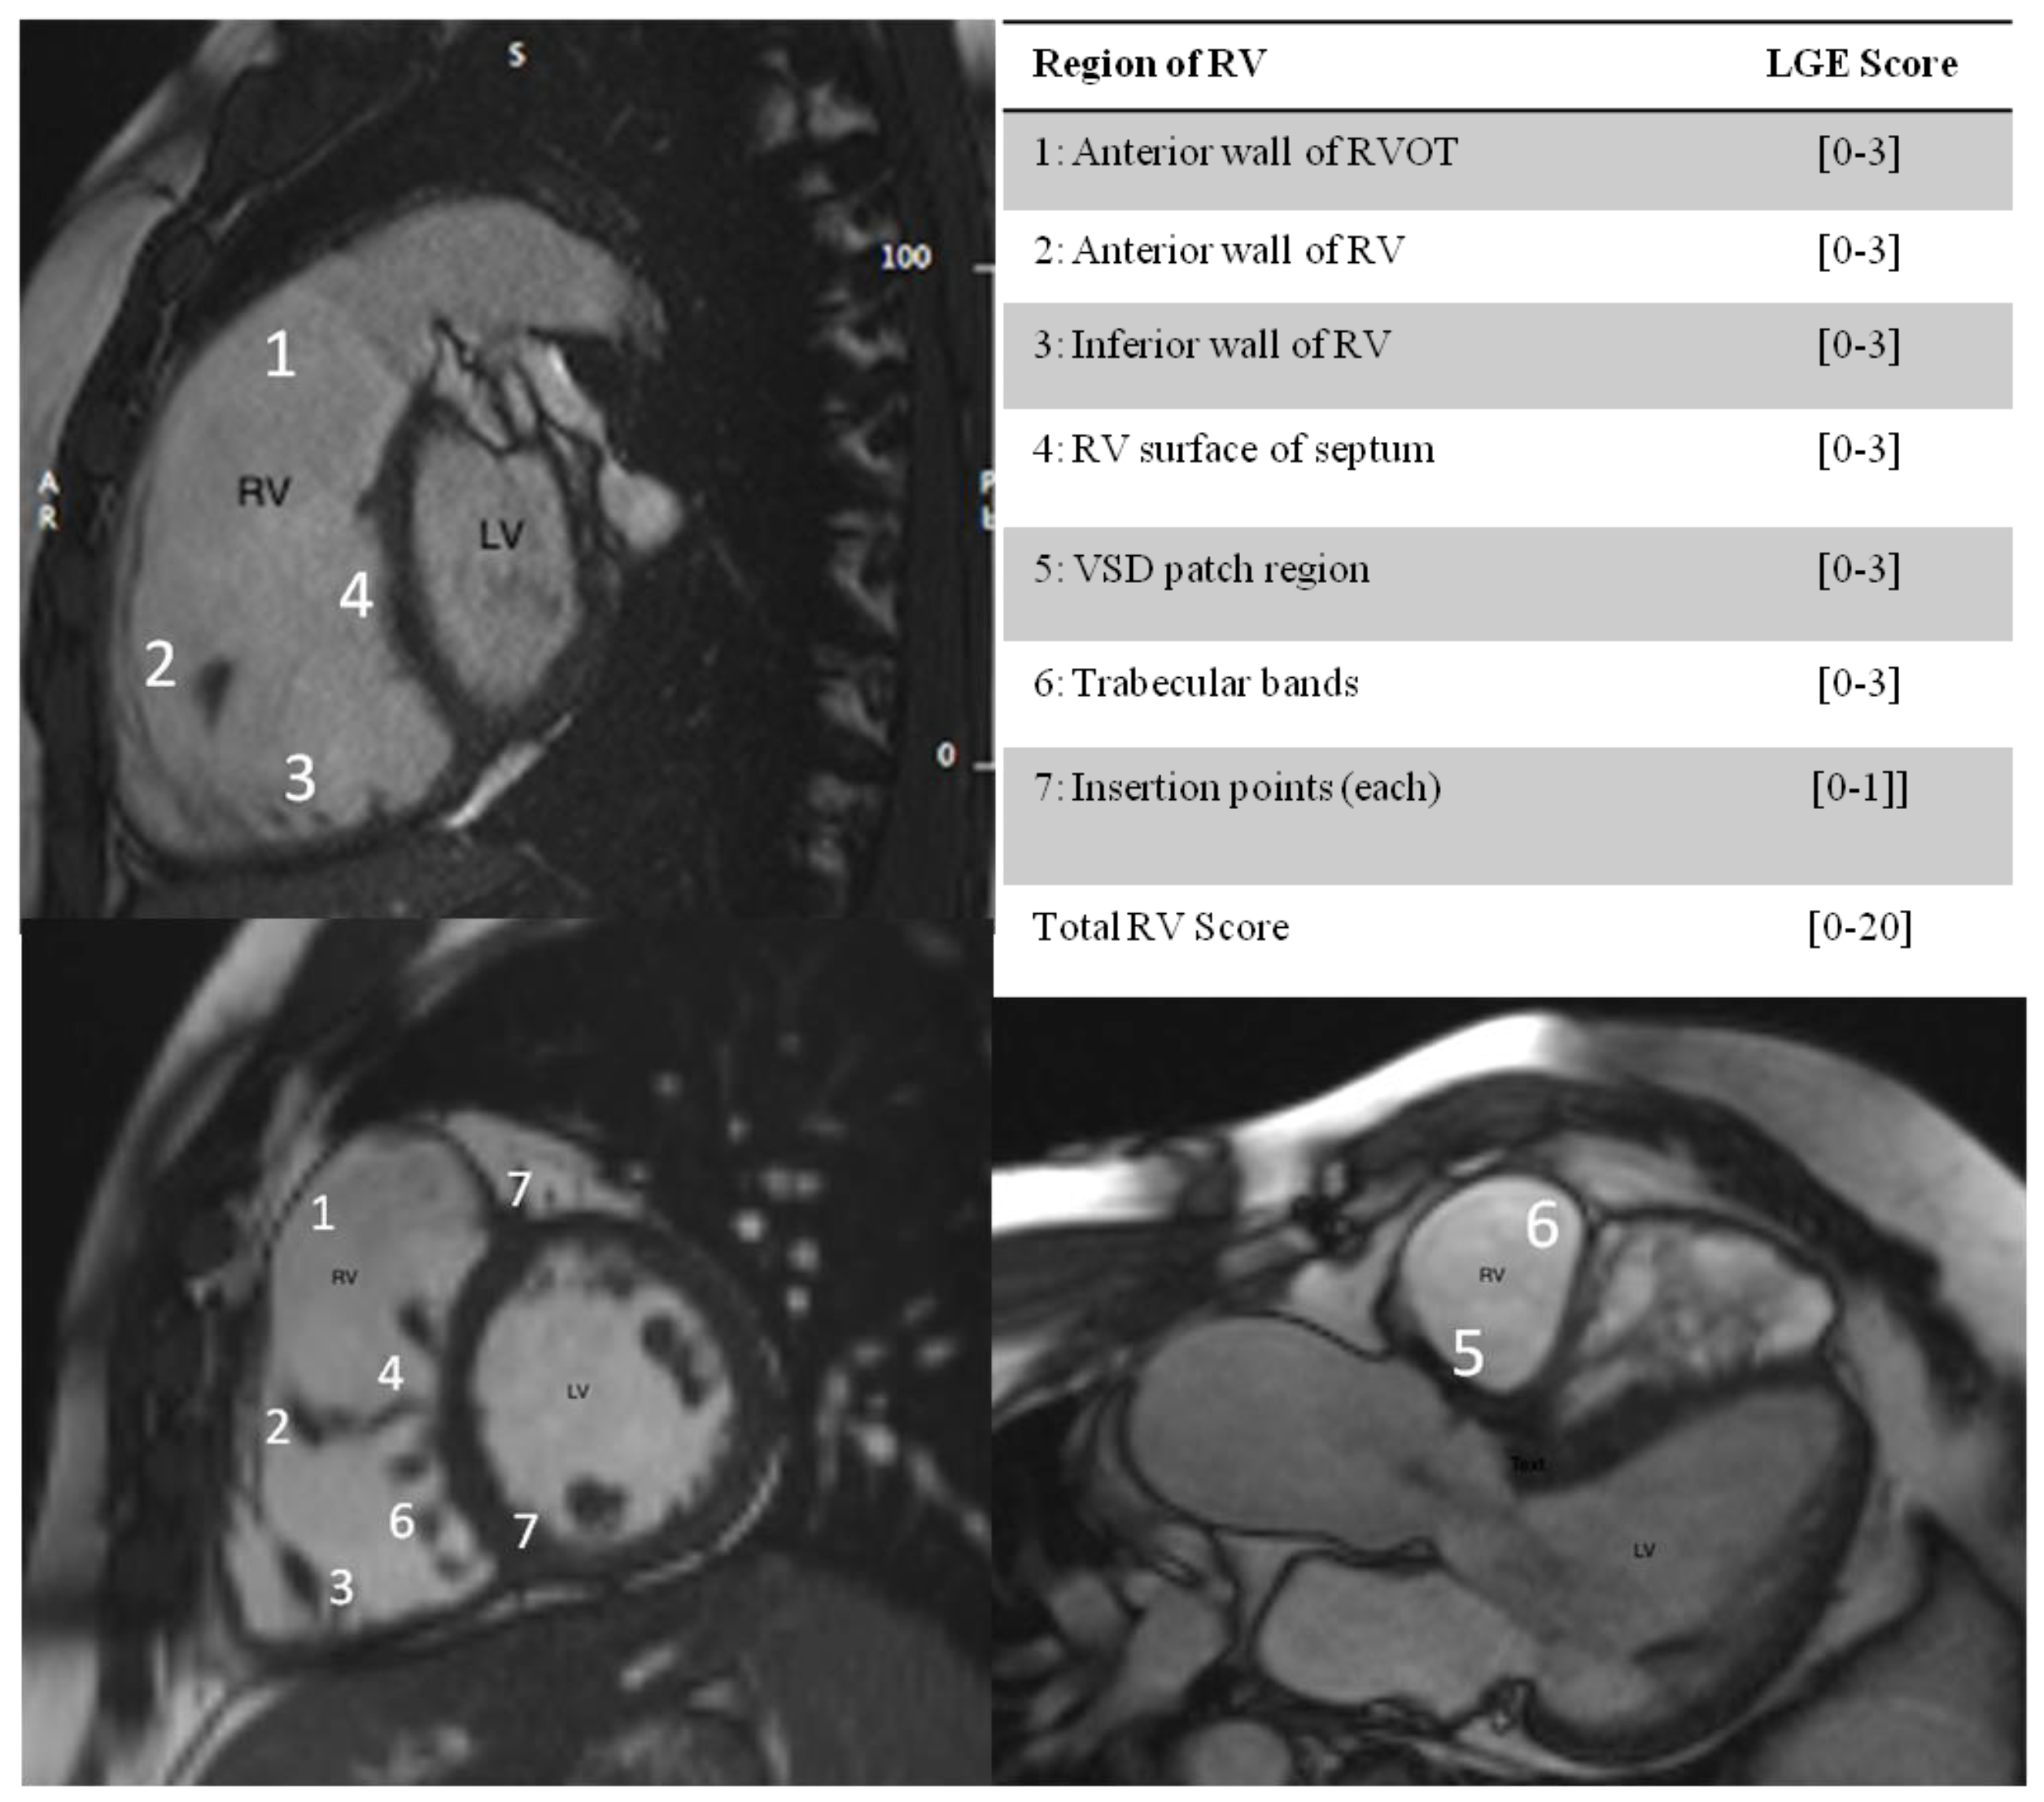

Gal-3 levels were higher in patients with supramedian LGE RV score but did not correlate with total LGE scoring of RV, p = 0.21, (Table 2). Gal-3 levels had a significant correlation with moderate/severe PR as estimated by PR Fraction > 20%, p < 0.044), (Supplementary Table S2). In ROC curve analysis, a cut-off value for Gal-3 of 7.42 ng/mL predicted PR Fraction >20% with specificity 93% and sensitivity 53% (AUC 0.704, (p = 0.05)) (Figure 2).

Figure 2.

In ROC curve analysis, a cut-off value for Gal-3 of 7.42 ng/mL predicted PR Fraction > 20% with specificity 93% and sensitivity 53% [AUC 0.704, (p = 0.05)].